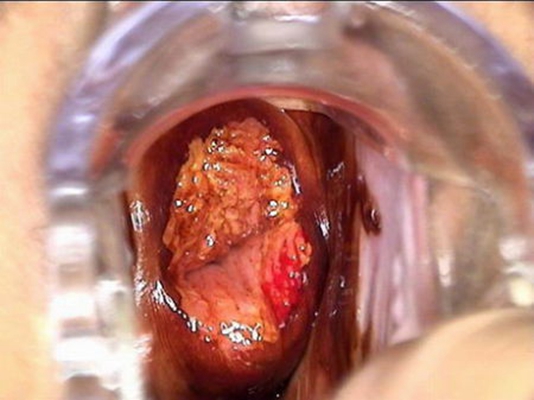

子宮頸癌前病變圖片

宮頸癌的早期症狀

宮頸癌的早期症狀

宮頸癌的早期症狀

宮頸癌的早期症狀

宮頸癌的早期症狀

宮頸癌的早期症狀

宮頸癌的早期症狀

宮頸癌的早期症狀

宮頸癌的早期症狀

宮頸癌的早期症狀